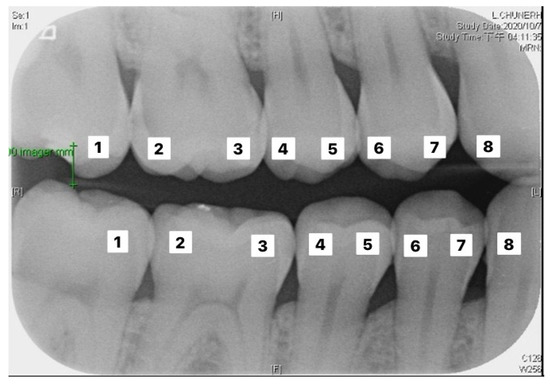

Figure 8 shows the importance of image preprocessing through the Gaussian filter and Otsu’s thresholding for image cropping.

Figure 8.

(a) Image processed through the Gaussian filter and Otsu’s thresholding, where the red line separates the upper and lower teeth; (b) image without any processing, where the red line separating the upper and lower teeth is very imprecise; (c) image processed only through Otsu’s thresholding, where the red line separating the upper and lower teeth is also imprecise.